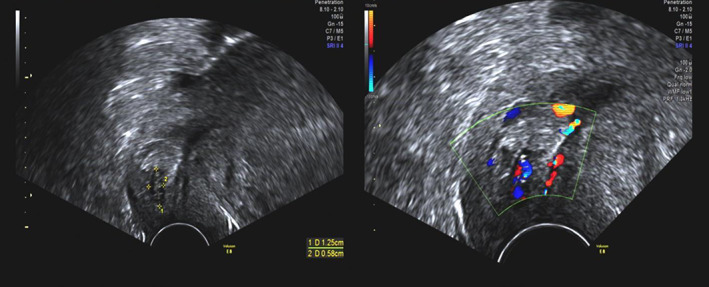

Ultrasound examination by an experienced ultrasound expert was conducted, besides the intrauterine gestational sac, there was a 12.5 × 5.8 mm abnormal echo in the cervical canal. Both of them had heartbeat and blood flow signals (Figure 2). Blood test showed that the hemoglobin was 125 g/L, the suspected diagnosis of heterotopic cervical pregnancy was confirmed (Figure 2). After counseling treatment options and risks, they preferred ultrasound‐guided aspiration to preserve the intrauterine pregnancy. The procedure lasted for 20 min, and blood loss was about 20 mL, then we oppressed the cervix with tranexamic acid‐soaked absorbable gauze for 20 min. Hemoglobin after aspiration was 121 g/L. The patient was discharged 24 h later. Ten days later, ultrasound showed one gestational sac in the uterine and CRL was 22.3 mm, with a heartbeat, and there was no abnormal echo in cervical canal. No vaginal bleeding was observed during pregnancy follow‐up and no other complications were found during gestation period inspection. She had a vaginal delivery of a male infant at 27 weeks because of premature rupture of membrane (PROM). The infant weight was 1240 g, and an Apgar score was 7 in 1 min. After 100 days of treatment in the neonatology department, the newborn was discharged with a bodyweight of 3600 g.

FIGURE 2.

Case 2 ultrasound imaging of cervical pregnancy at the time of diagnosis